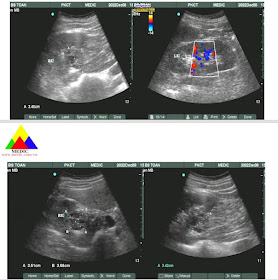

Ultrasound detected two echoic masses #35x17mm and 25x13 mm into her gallbladder and GB wall thickening #13 mm. There were some lymph nodes at the liver hilus and the pancreatic head.